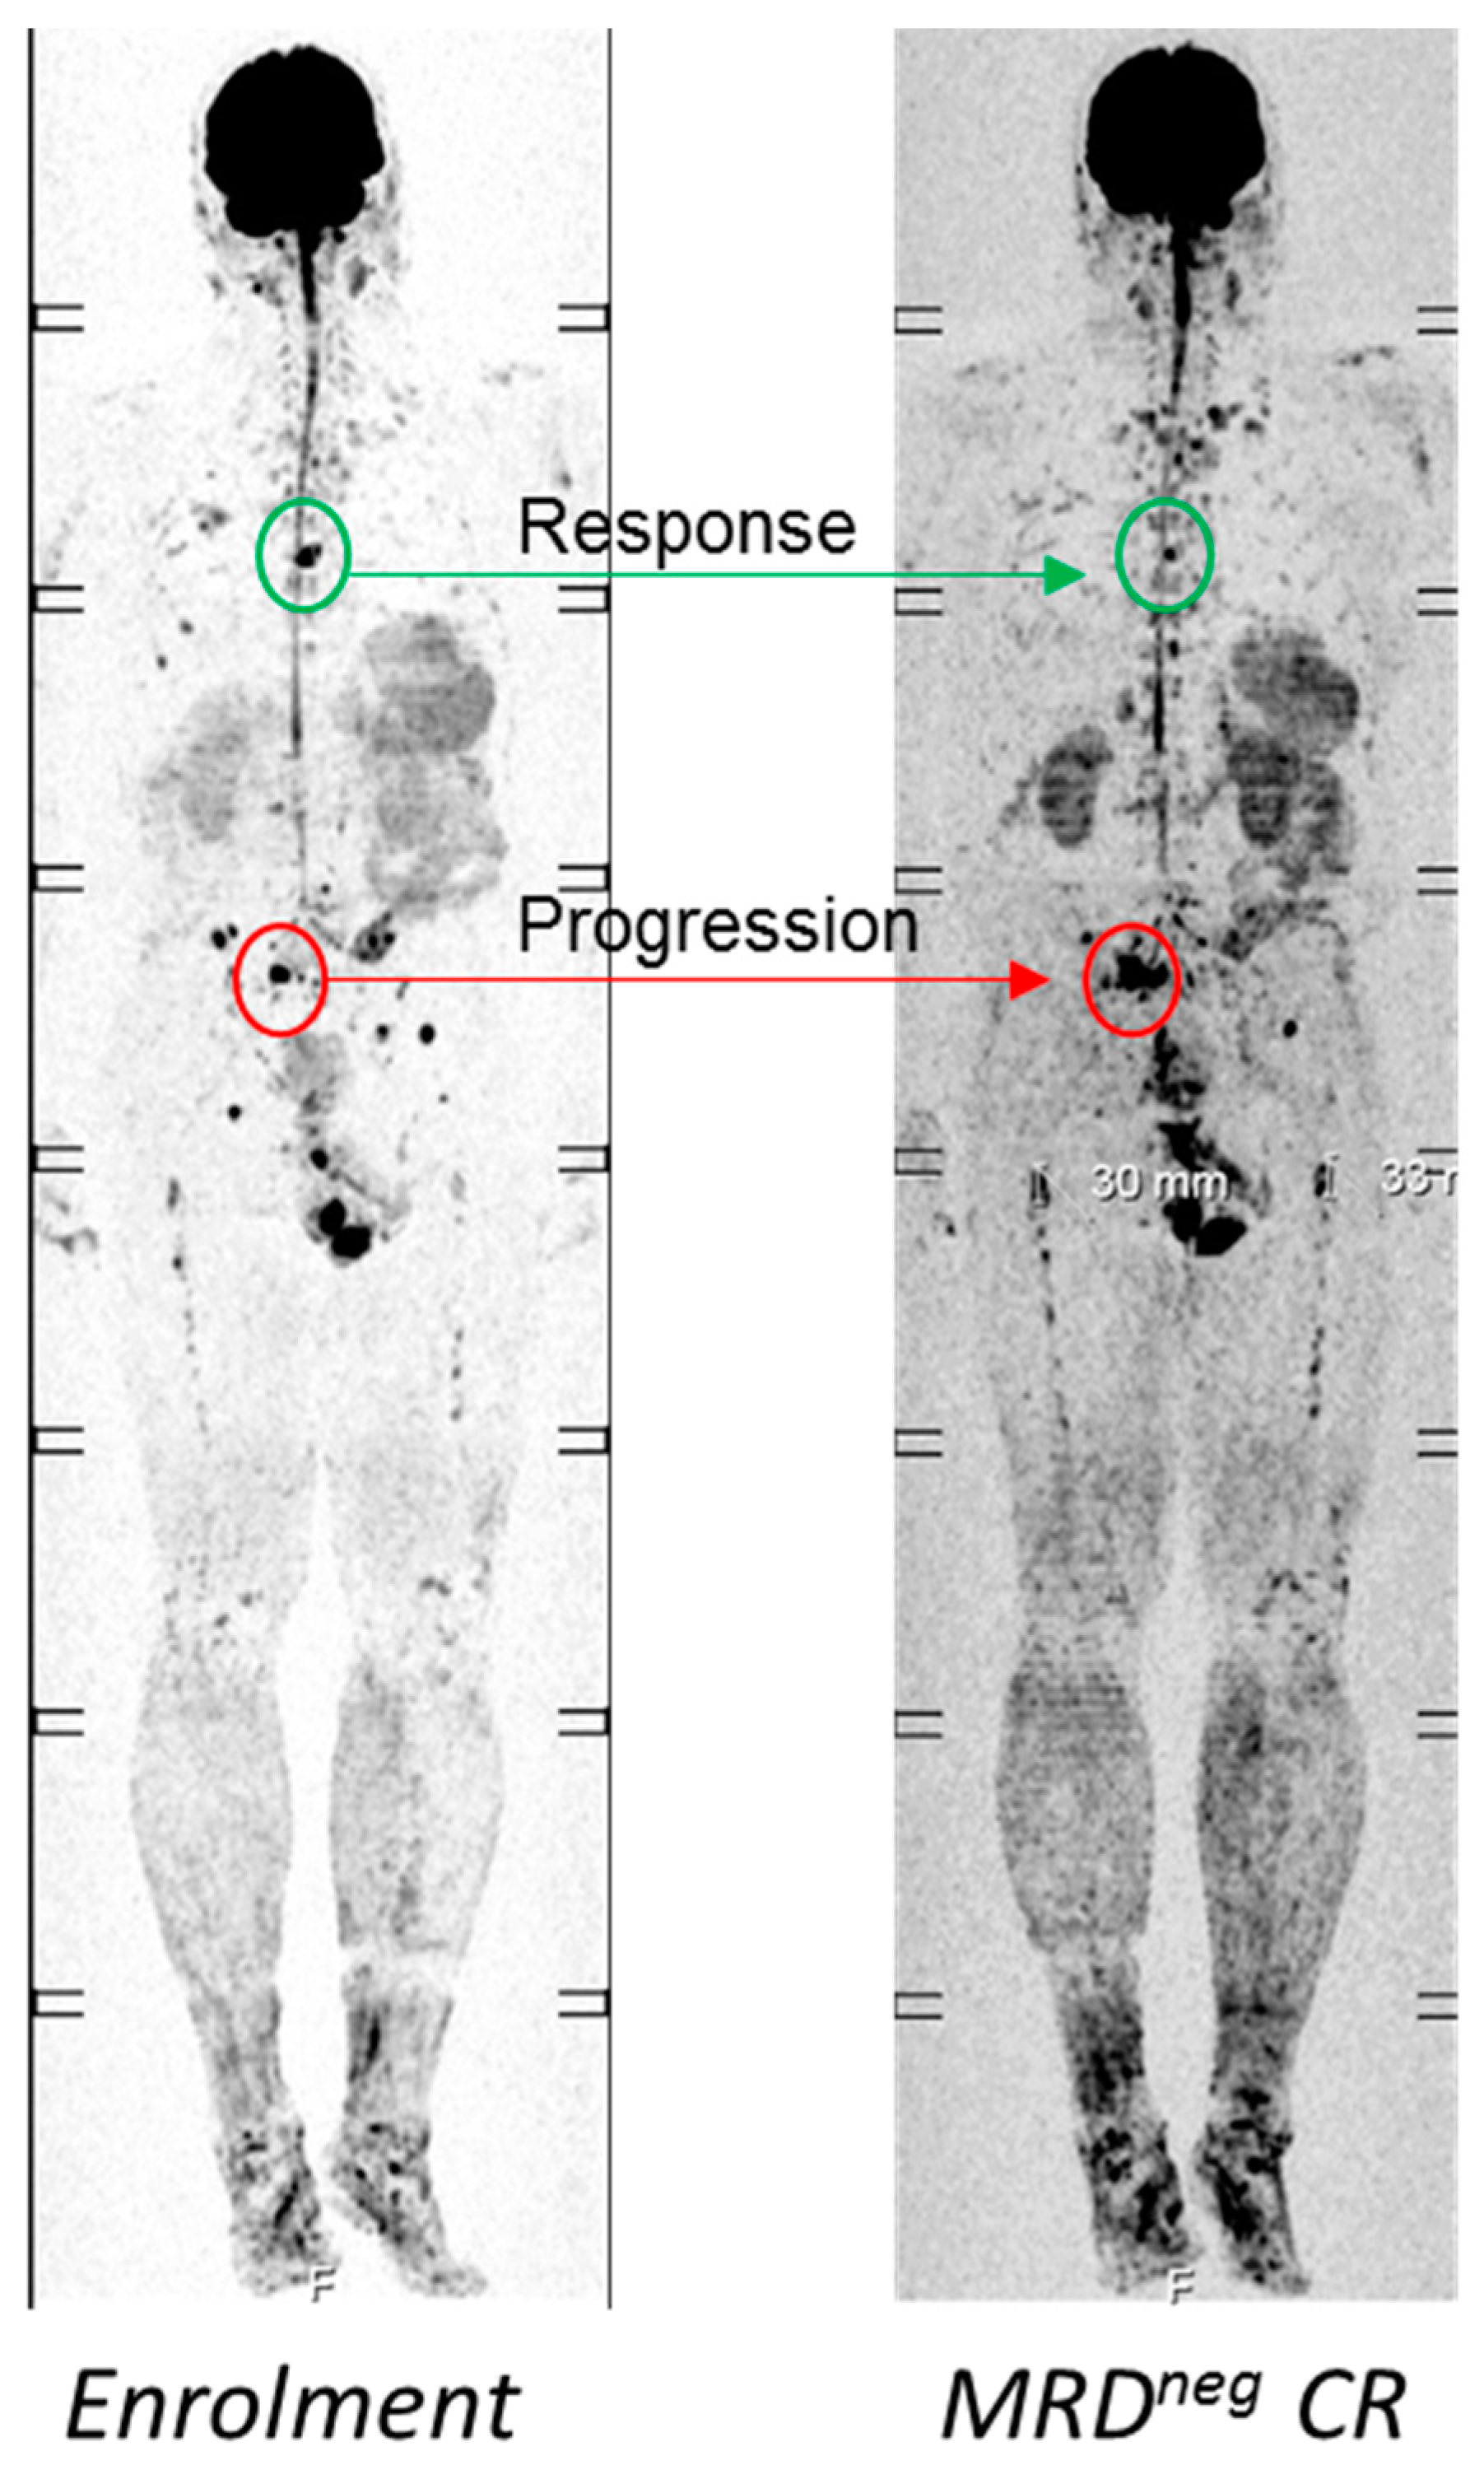

- Rasche, L.; Alapat, D.; Kumar, M.; Gershner, G.; McDonald, J.; Wardell, C.P.; Samant, R.; Van Hemert, R.; Epstein, J.; Williams, A.F.; et al. Combination of flow cytometry and functional imaging for monitoring of residual disease in myeloma. Leukemia 2018. [Google Scholar] [CrossRef]

- Davies, F.E.; Rosenthal, A.; Rasche, L.; Petty, N.M.; McDonald, J.E.; Ntambi, J.A.; Steward, D.M.; Panozzo, S.B.; van Rhee, F.; Zangari, M.; et al. Treatment to suppression of focal lesions on positron emission tomography-computed tomography is a therapeutic goal in newly diagnosed multiple myeloma. Haematologica 2018, 103, 1047–1053. [Google Scholar] [CrossRef]